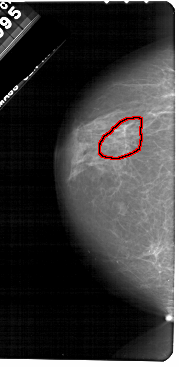

A_1651_1.LEFT_MLO

FILE: A_1651_1.LEFT_MLO.OVERLAY

TOTAL_ABNORMALITIES 1

ABNORMALITY 1

LESION_TYPE CALCIFICATION TYPE PLEOMORPHIC DISTRIBUTION LINEAR

ASSESSMENT 4

SUBTLETY 1

PATHOLOGY BENIGN

TOTAL_OUTLINES 1

BOUNDARY